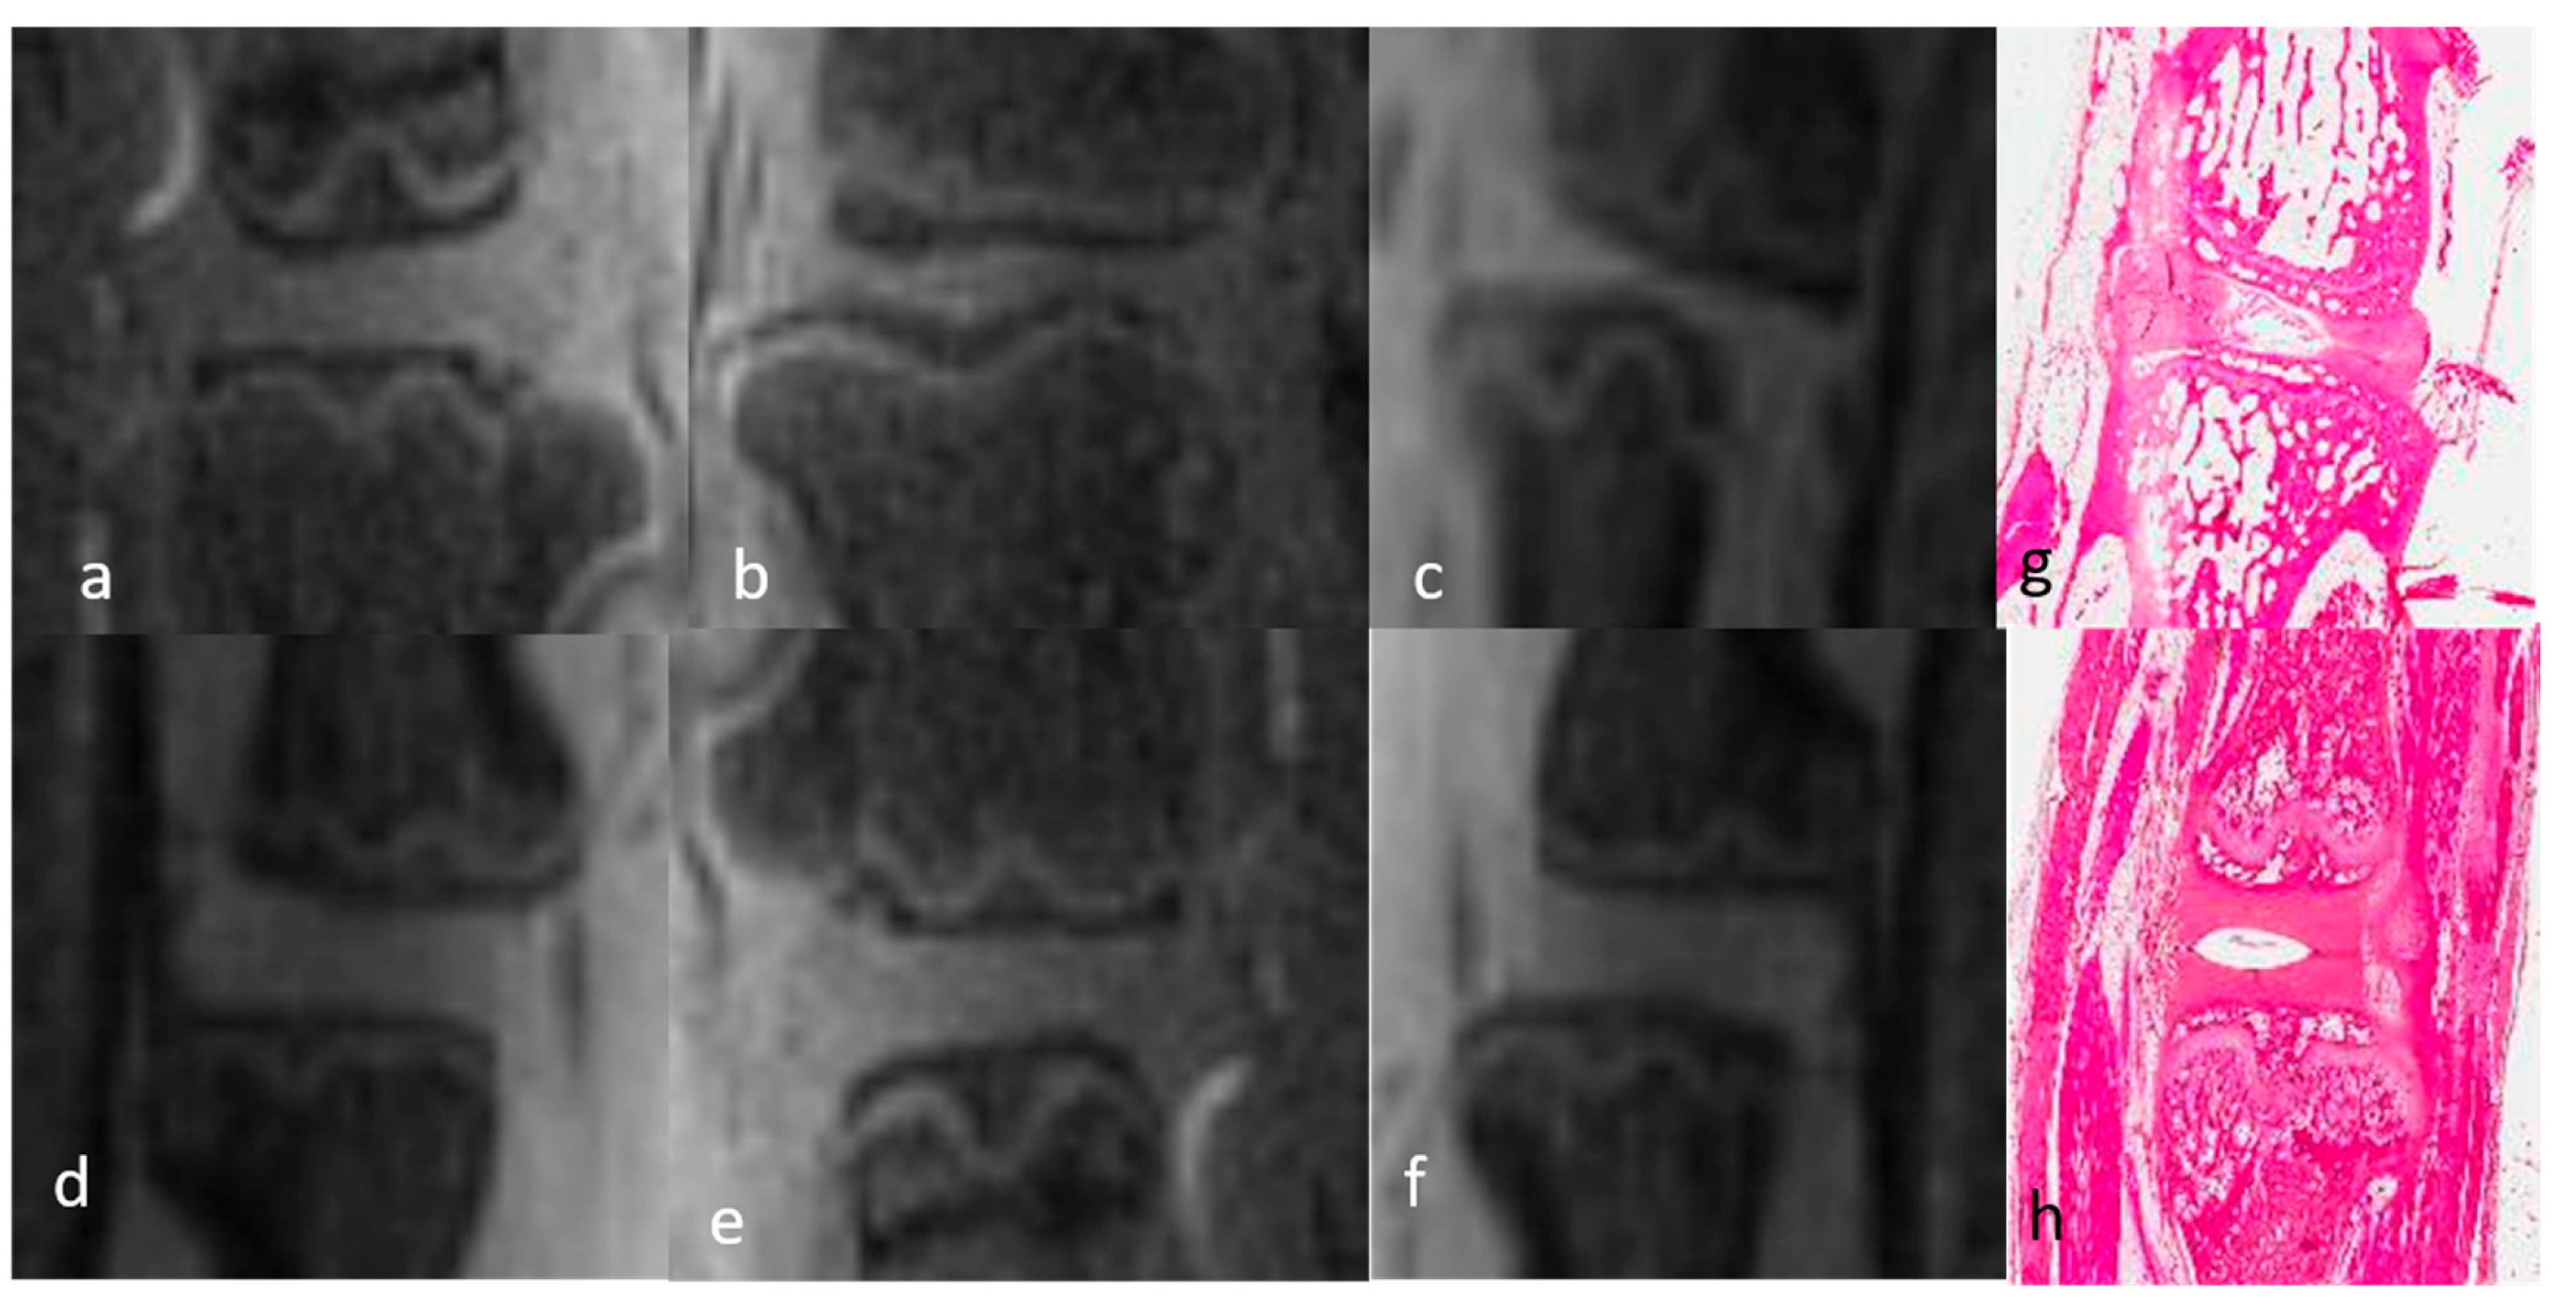

3.1.2. Qualitative Analysis of the DVC in DDD Rats (Table 3)

3.1.1. Qualitative Analysis of the Normal DVC (Table 1 and Table 2)